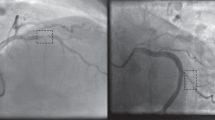

Screening for coronary artery disease is a major health issue, knowing that the most common cause of death in industrialized countries is cardiovascular pathology (coronary artery disease, stroke, other cardiovascular diseases). Computer Aided Diagnosis systems (CADx) can assist cardiologists to and play a key role in detecting abnormalities and treating coronary arteries. In this paper we propose a deep learning classification method based on a new Hybrid CNN-LSTM Architecture. The aim of our method is to detect the presence of stenosis in the coronary arteries and to classify the type of arteries. Our experiments have been conducted using an anonymized database from a Belgian hospital (CHR Mons-Hainaut) thanks to a retrospective study.